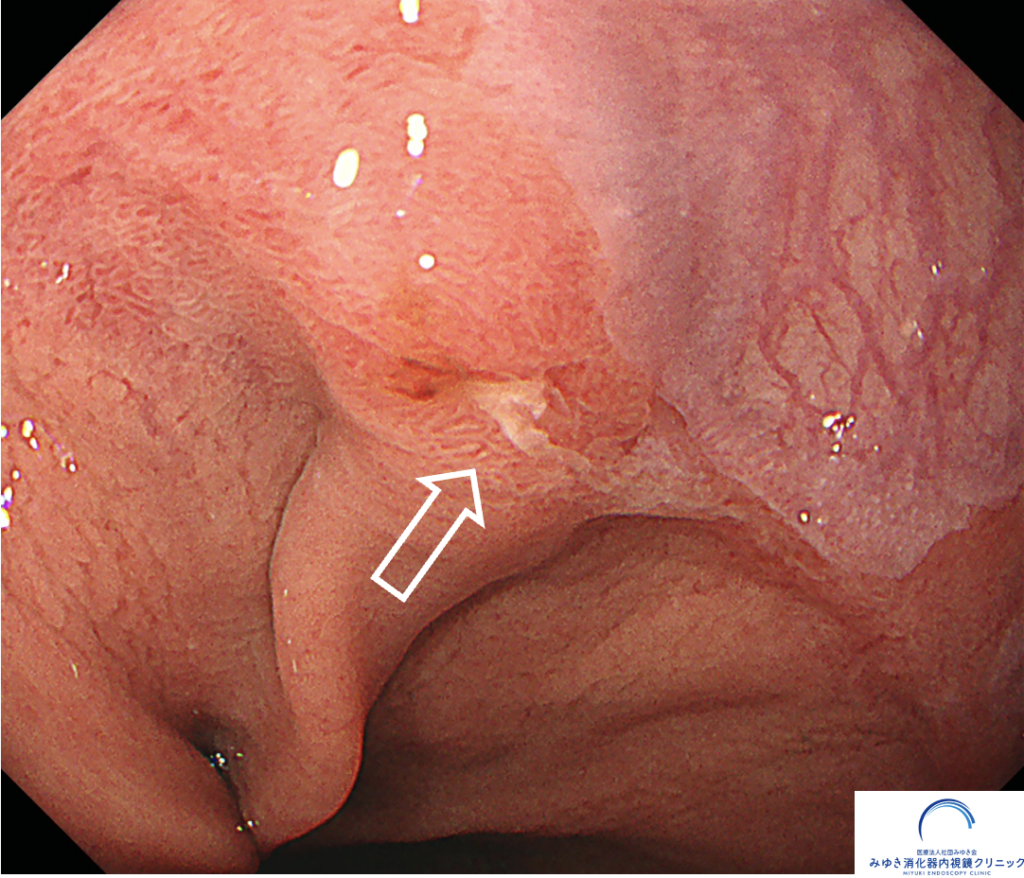

ある検査の際、バレット食道の部分にごく小さな「へこみ(陥凹)」と軽い出血が見つかりました。

NBI観察

生検(組織検査)を行ったところ、がん細胞が確認されました。

早期発見だったため、大学病院で内視鏡的粘膜下層剥離術(ESD)という内視鏡治療を受け、がんは完全に取りきれました。その後も定期的に胃カメラでフォローしています。